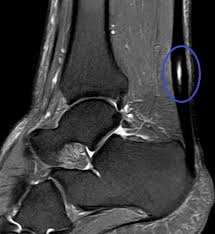

Für die erste Übung begib dich in den Vierfüßlerstand. Ein MRI zeigte eine typische spindelförmige Verdickung der Sehne jedoch keine fortgeschrittene Degeneration der Sehnensubstanz selbst. Stelle dich an eine Wand und stütze dich mit beiden Armen nach vorne ausgestreckt an ihr ab.

Typisch ist ein Druckschmerz am Ansatz der Achillessehne sowie eine Verdickung Rötung oder Schwellung der Sehne. Wenn ein knöcherner Vorsprung an der Oberkante Ihres Fersenbeins zu einer Reizung der Sehne führt nennt man das Haglund-Exostose. Manche Betroffene klagen insbesondere beim Aufwärmen über Schmerzen. Mit zunehmendem Alter werden durch Verschleiß der Fasern unsere Sehnen schwächer. Ein MRI zeigte eine typische spindelförmige Verdickung der Sehne jedoch keine fortgeschrittene Degeneration der Sehnensubstanz selbst. Bei vielen Menschen stellt die Achillesferse daher den neuralgischen Punkt dar. Besonders durch die Reibung der Strukturen und die Entzündung der sehr empfindlichen Knochenhaut entstehen diese Schmerzen. Die gereizte Achillessehne ruft die Entzündungsreaktion hervor. Die entzündete Achillessehne ihr Ansatz am Fersenbein und das umgebende Gewebe sind gereizt.